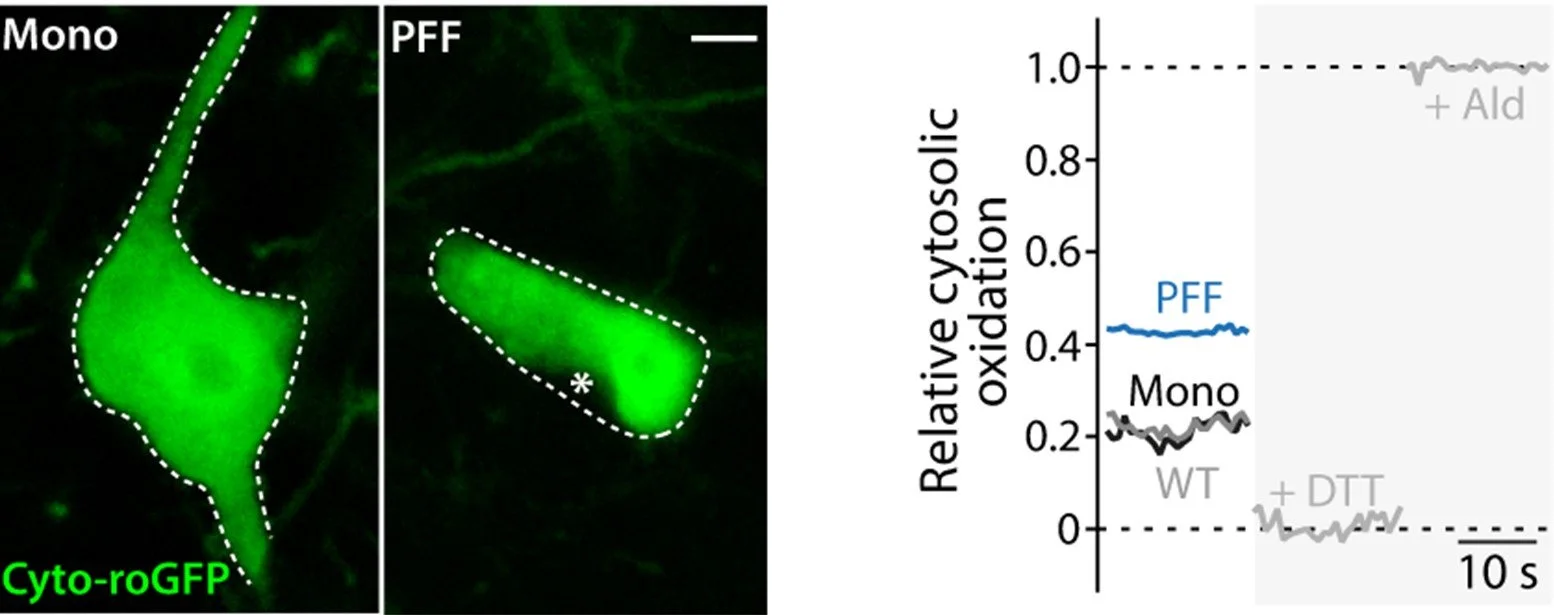

Intracellular aggregation of the small protein α-synuclein is a hallmark of Parkinson’s disease and thought to be responsible for the progressive loss of neurons. By combining up-to-date biosensors with two-photon-laser-scanning-microscopy we investigate how Lewy pathology causes neurons to die in Parkinson’s disease.

By combining redox-sensitive biosensors with two-photon-laser-scanning-microscopy the oxidative state of neurons can be measured.

Robust disease models are at the core of high-quality translational Parkinson’s disease research. Scientists at the CNP lab are continuously making progress in further characterizing the two central α-synuclein based Parkinson’s disease models: The α-synuclein preformed fibril model and the viral vector based α-synuclein overexpression model.